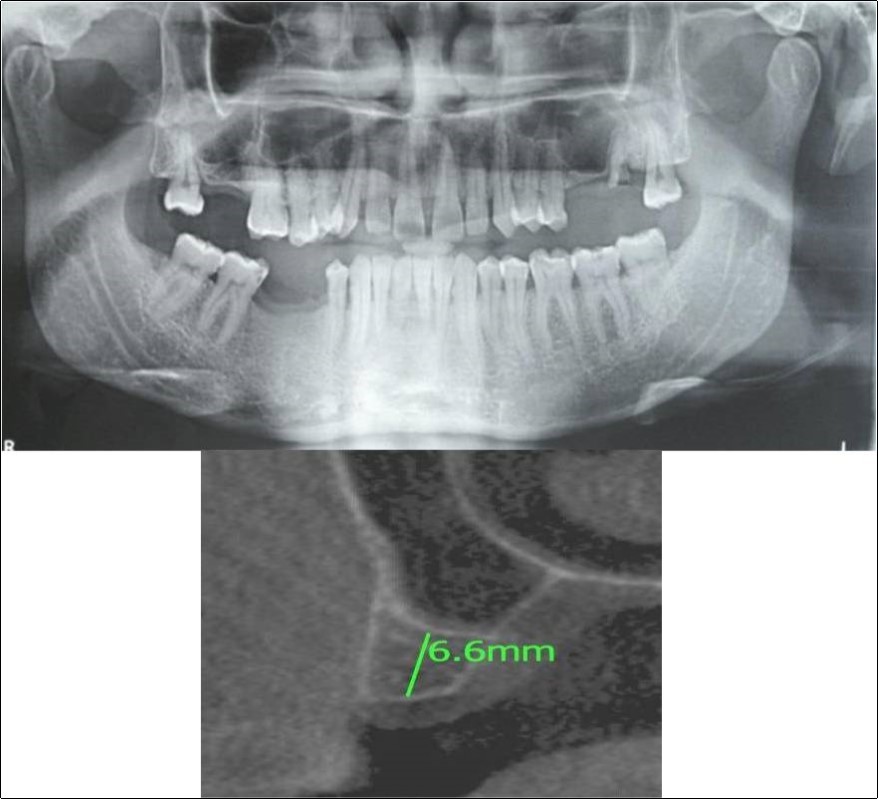

Clinical and Radiological Assessment:

1.Partially edentulous maxillary and mandibular arches with missing 17, 26, 45, 46;

2.Increased pneumatisation of right maxillary sinus;

3.Height of available bone- 6.6mm;

4.Transverse thickness of available bone (CBCT evaluation)- 11mm;

5.Inter-ridge space adequate to place implant (10mm).

Figure 11.(a,b) Pre-treatment OPG and cross section of CBCT showing residual alveolar bone height for Case No.3

Figure 12.(a,b) Post-treatment OPG and cross section of CBCT showing residual alveolar bone height for Case No.3;